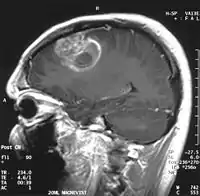

En las imágenes de TC y RM se muestra como una lesión heterogénea, de contorno irregular, que capta contraste en anillo y con un área central necrótica.

La TC muestra una lesión de morfología irregular, predominantemente hipodensa y fuertemente dishomogénea, debido a la presencia de grandes áreas necróticas de más clara hipodensidad y de áreas sólidas hiperdensas. Estas últimas son la expresión de un rápido crecimiento y por lo tanto de una elevada malignidad. Son frecuentes las zonas hemorrágicas, que van desde pequeños focos a grandes áreas hemáticas que pueden cubrir toda la lesión. Es característica la morfología en "mariposa" si el tumor se asienta en ambos hemisferios a través del cuerpo calloso.

Tras la aplicación de contraste aparecen gruesos anillos alrededor de las áreas necróticas. En la RM, la parte sólida aparece hipointensa en T1 e hiperintensa en T2 con zonas de señal más elevada en las partes de mayor celularidad. Las áreas necróticas, hiperintensas en T2, pueden presentarse hipo-, iso- o hiperintensas en T1 en función del contenido proteico o de productos de la degradación de la hemoglobina. El realce tras el contraste suele ser intenso e irregular en la periferia del tumor e identifica sobre todo la componente celular "proliferativa" de la neoplasia. Son comunes las áreas puntiformes y serpiginosas de ausencia de señal de flujo, asociadas a la presencia de una neovascularización rica. Estos vasos de neoformación patológica carecen de barrera hematoencefálica, lo que explica tanto la abundante impregnación como el edema vasogénico perilesional (véase la sección anterior), debido al paso de líquido al medio extracelular.[71][72]